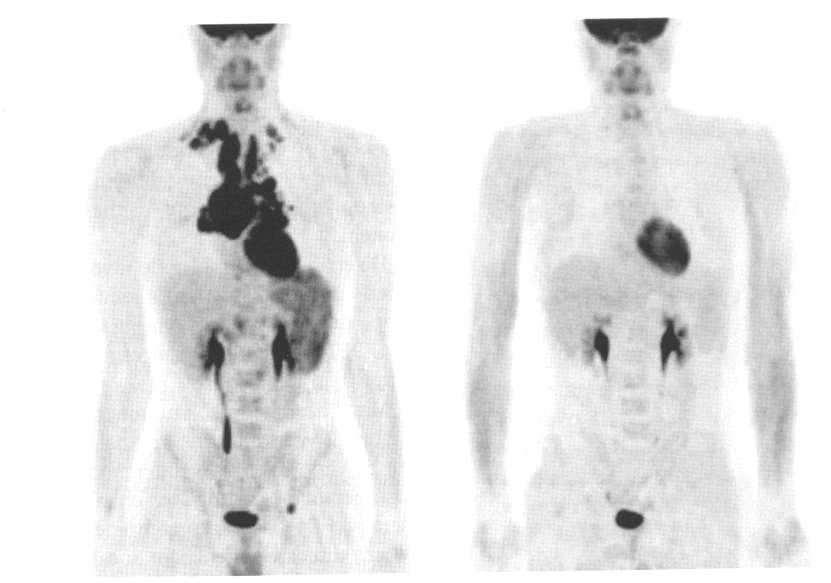

this image shows pre and post breast cancer monitoring (pre and post chemotherapy)

the image on the left is initial, 3 months or 5 months

initial

the image in the middle is initial, 3 months or 5 months

3 months

the image on the right is initial, 3 months or 5 months

5 months